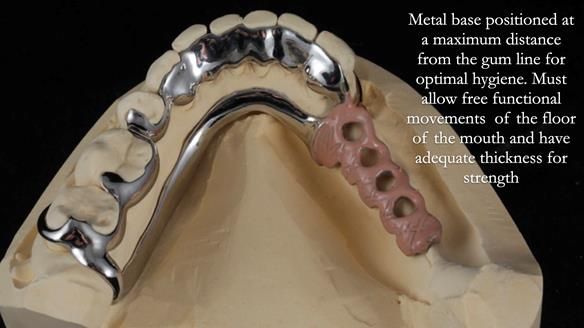

In 2024, my resolution is to revolutionise global teaching and design of partial dentures. I've been inspired by the hygienic Scandinavian approach to RPD design by John Besford, Charlotte Stilwell and Linda Blakely. Since implementing this method, my patients now only need 1.5 reviews after fitting, a significant improvement compared to the 5 reviews required using the the RPI system I was originally taught. It has notably improved the quality of life for my patients. I'm reaching out to you for support in achieving this goal by sharing my newsletters with dentists and educators globally. Together, we can spread this innovative approach worldwide. Your assistance is crucial in making a significant impact.

I explain the hygienic Scandinavian partial design system in this lecture, starting from the 21-minute mark in the video. To watch this segment, please click on the thumbnail below.